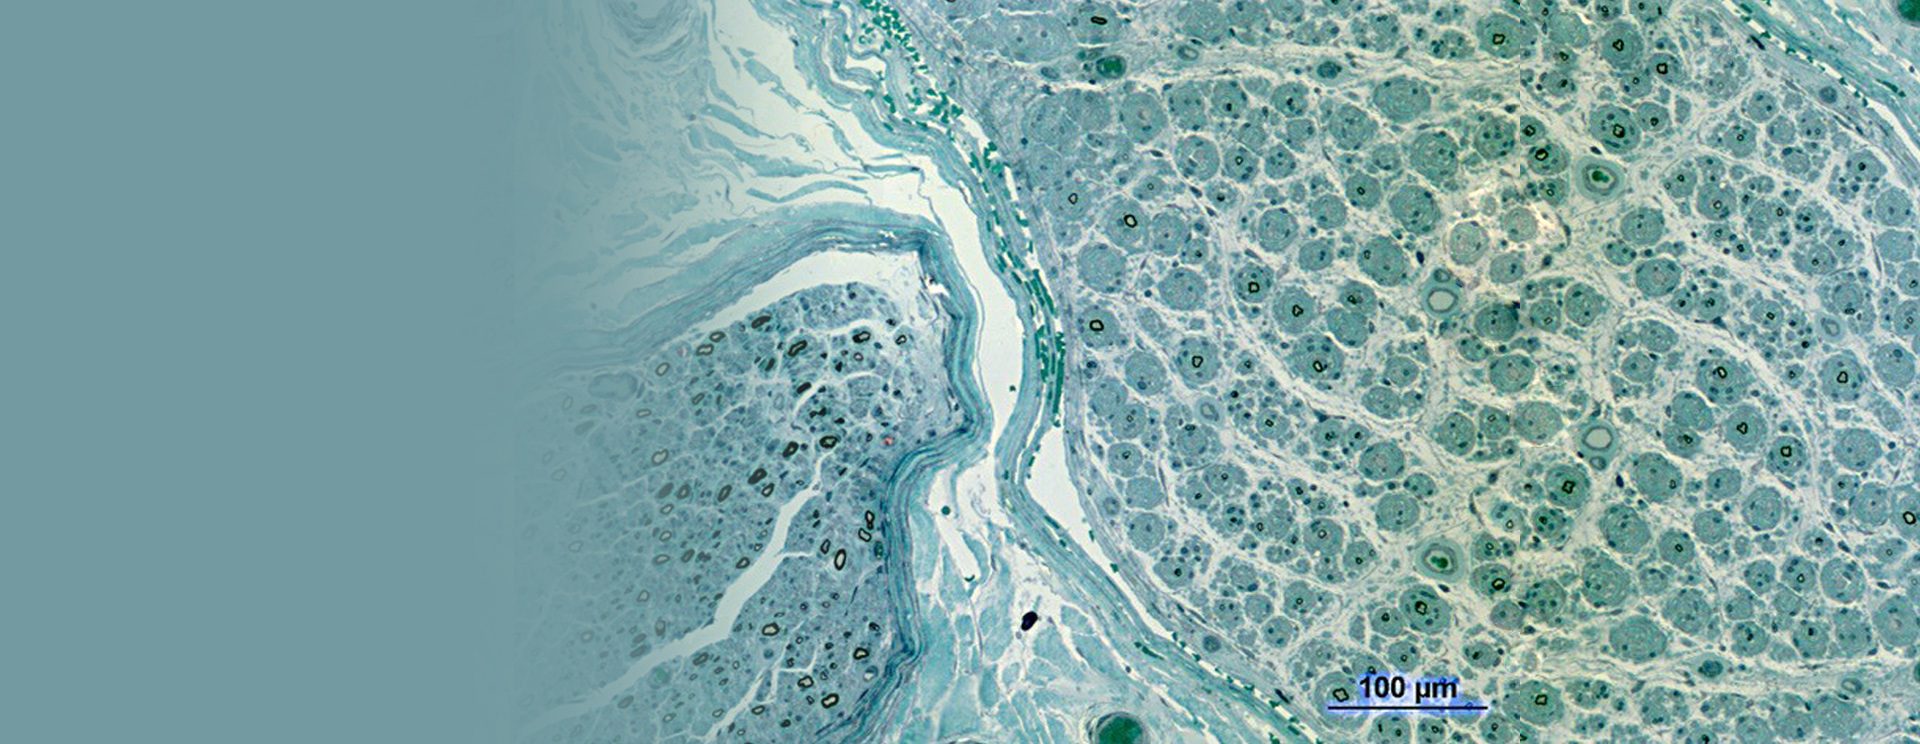

• Interprétation de biopsies

En collaboration avec le service d’Anatomie Pathologique, notre centre assure l’analyse experte :

• Des biopsies nerveuses, musculaires et cutanées

• Y compris pour des prélèvements réalisés dans d’autres centres en France

• Biopsies nerveuses, musculaires et cutanées